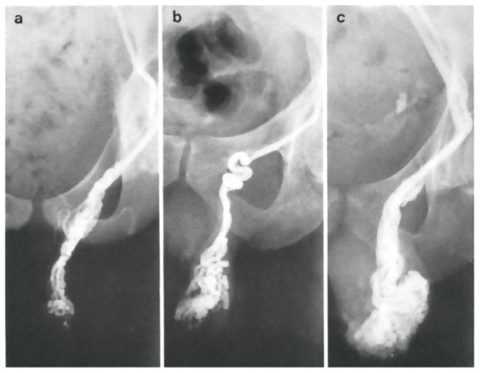

Для определения степени выраженности варикоцеле врач ощупывает мошонку и назначает рентгенологическую диагностику: антеградную флеботестикулографию или ретроградную почечную флебографию, предварительно при этом вводят контрастное вещество в вену мошонки.

Эндоваскулярную облитерацию (окклюзию) вены яичка проводят взрослым и детям спиральными эмболами, проволочными зонтикообразными устройствами, баллонами, тканевым клеем, препаратами для склерозирования вены.